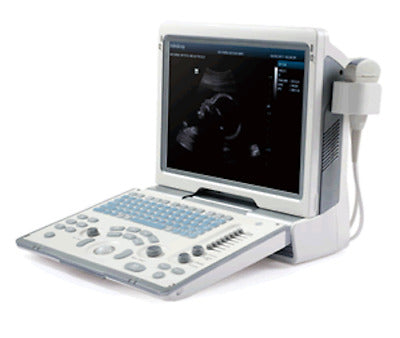

MINDRAY DIGITAL ULTRASOUND DIAGNOSTIC IMAGING SYSTEM,GREAT CONDITION(DP-50)

Sale price$ 5,250.00

Regular price$ 5,600.00

MINDRAY DP-50 PORTABLE ULTRASOUND WITH ONE CHOICE PROBE 1 YEAR WARRANTY

Sale price$ 5,998.00

Regular price$ 6,398.00

Save $ 676.00

MINDRAY DP-50 ULTRASOUND SYSTEM WITH ONE TRANSDUCER

Sale price$ 10,132.00

Regular price$ 10,808.00

Mindray DP-50 Ultrasound with Linear Transducer

Sale price$ 19,743.99

Save $ 170.00

Mindray DP50 Ultrasound with Convex Probe 35C50EA

Sale price$ 8,248.00

Regular price$ 8,798.00

Save $ 700.00

Mindray DP50 Ultrasound with Linear Array Probe 75L38EA

Sale price$ 10,498.00

Regular price$ 11,198.00